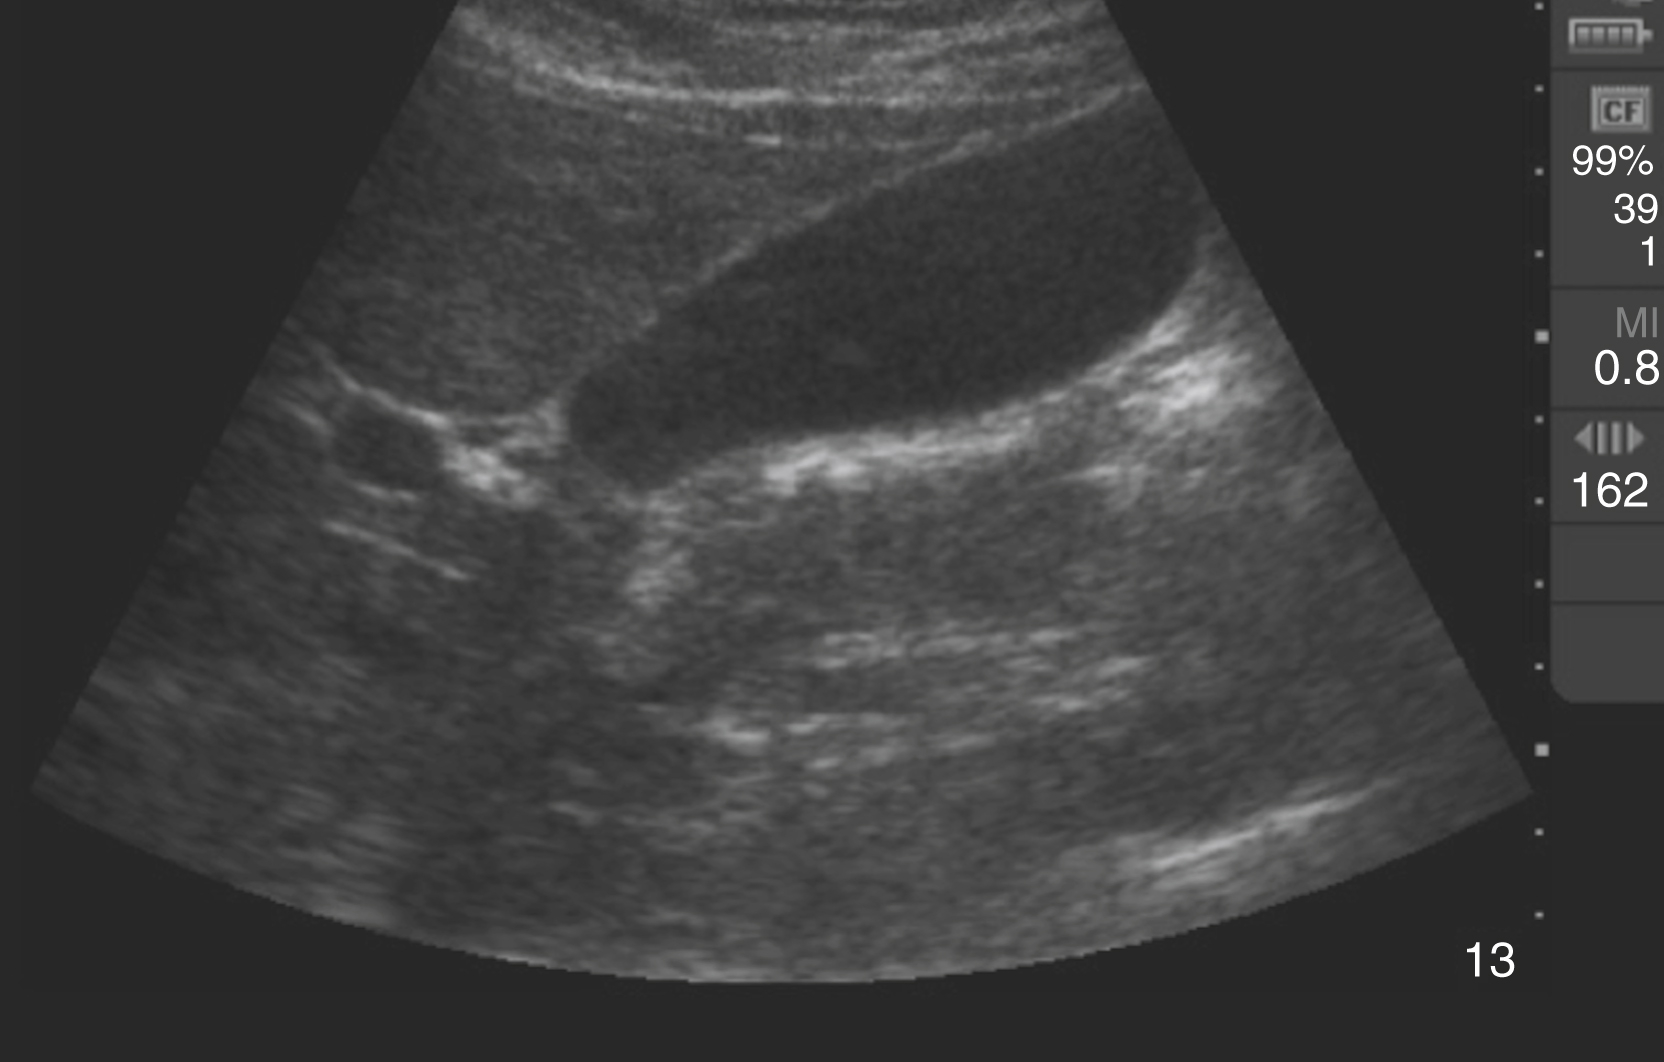

Pathology

Hydronephrosis is characterized by dilation and anechoic fluid accumulation within the renal pelvis and calyces, ranging from mild to severe ( Fig. e3.6 ). Renal and/or ureteral calculi may be identified as echogenic foci with associated shadowing and are usually located within the kidney (nonobstructive) or in the renal pelvis, proximal ureter, or uretero-vesicular junction. Color Doppler placed over the kidney can help differentiate mild hydronephrosis from the renal vasculature, as well as possibly accentuate any renal stones by producing the renal twinkle artifact.

Fig. e3.6

Hydronephrosis with dilation of the calyces and renal pelvis of the kidney showing thinning of the cortex, signifying severe hydronephrosis.